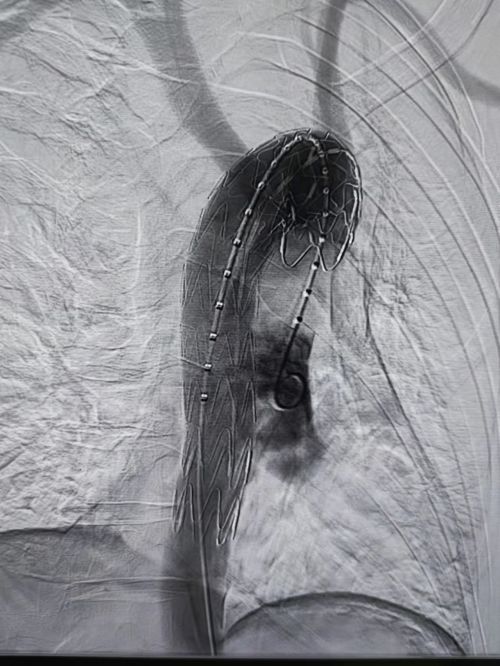

介入血管外科王庆主任、张昊医师等为患者施行主动脉假性动脉瘤腔内修复术。

术后,假性动脉瘤消失。

完善术前相关检查及准备后,王庆、姚袁晖、张昊等于2月24日晚21时许,在局麻下为患者施行主动脉假性动脉瘤腔内修复术。手术历时约15分钟,术后复查造影显示:主动脉支架位置良好,假性动脉瘤显影完全消失,未出现支架内漏或外渗,头颈部及其他重要血管血供未受影响。